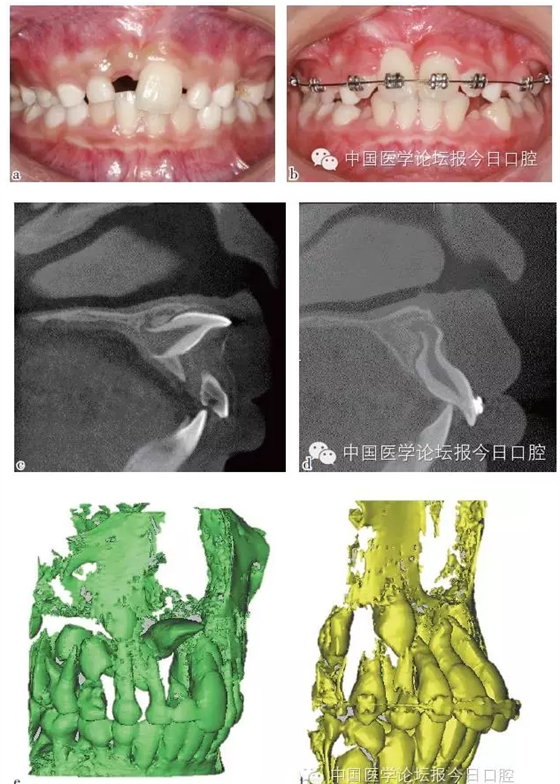

彎根牙的牽引助萌常受到彎根嚴(yán)重程度及彎根角度的影響,早期牽引能引導(dǎo)牙根形成方向,降低牙根彎曲的嚴(yán)重程度。

如病例二(圖2)所示,11彎根牙行早期牽引,11牙根繼續(xù)發(fā)育、彎曲程度減小。

圖2 11彎根牙行早期牽引;11牙根繼續(xù)發(fā)育,牙根彎曲程度減小